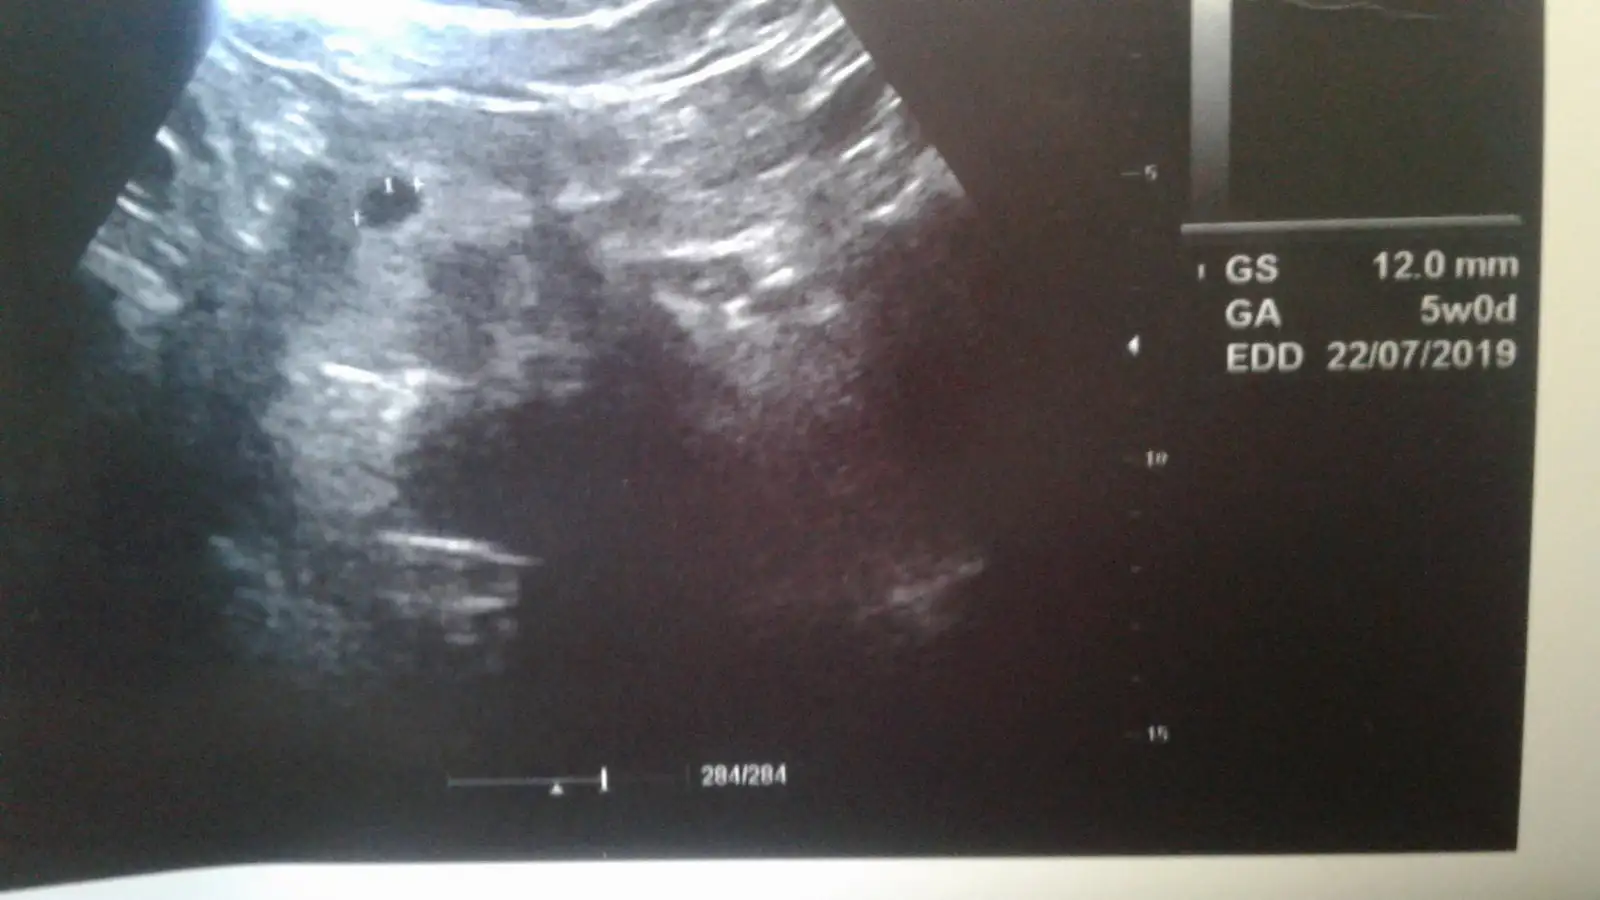

Karından Ise Sağa Yakın Kız Gibi Tatlım Kacinci Haftandasın Şuanben attım![]()

karından canım 7+2 deyim :)Karından Ise Sağa Yakın Kız Gibi Tatlım Kacinci Haftandasın Şuan

Bu benim minnoş kesem.Bebeğin yönüne Gore Keseye Gore En cok Hangi Tarafa Yakinsa.Ona.Gore Sekline Goree

Yesinler Masallah Kuzularimiza Ama Bisey Goremedim Kesen Solda Bakalim Bebeside Gorursek Ona Gore Soyleyelim Olurmu Suan Net Degil ❤Bu benim minnoş kesem.![]()